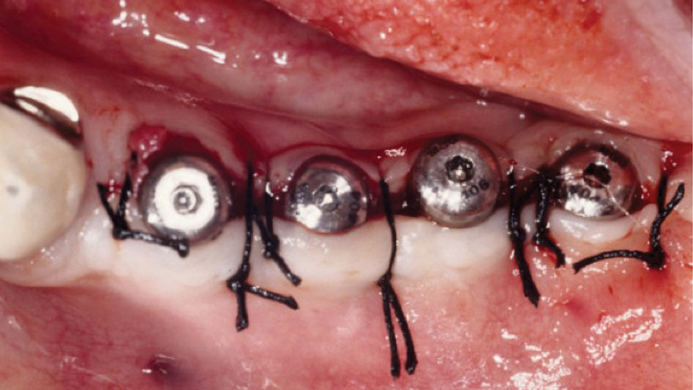

Thanks to MegaGen’s unique KnifeThread® and super self-tapping design, better initial stability can be attained in any compromised bone situation.

The design enables bone condensing, gentle ridge expansion, maximized compressive force resistance, and minimized shear force production.